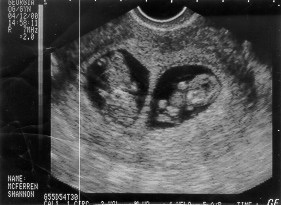

For these children I did pray!